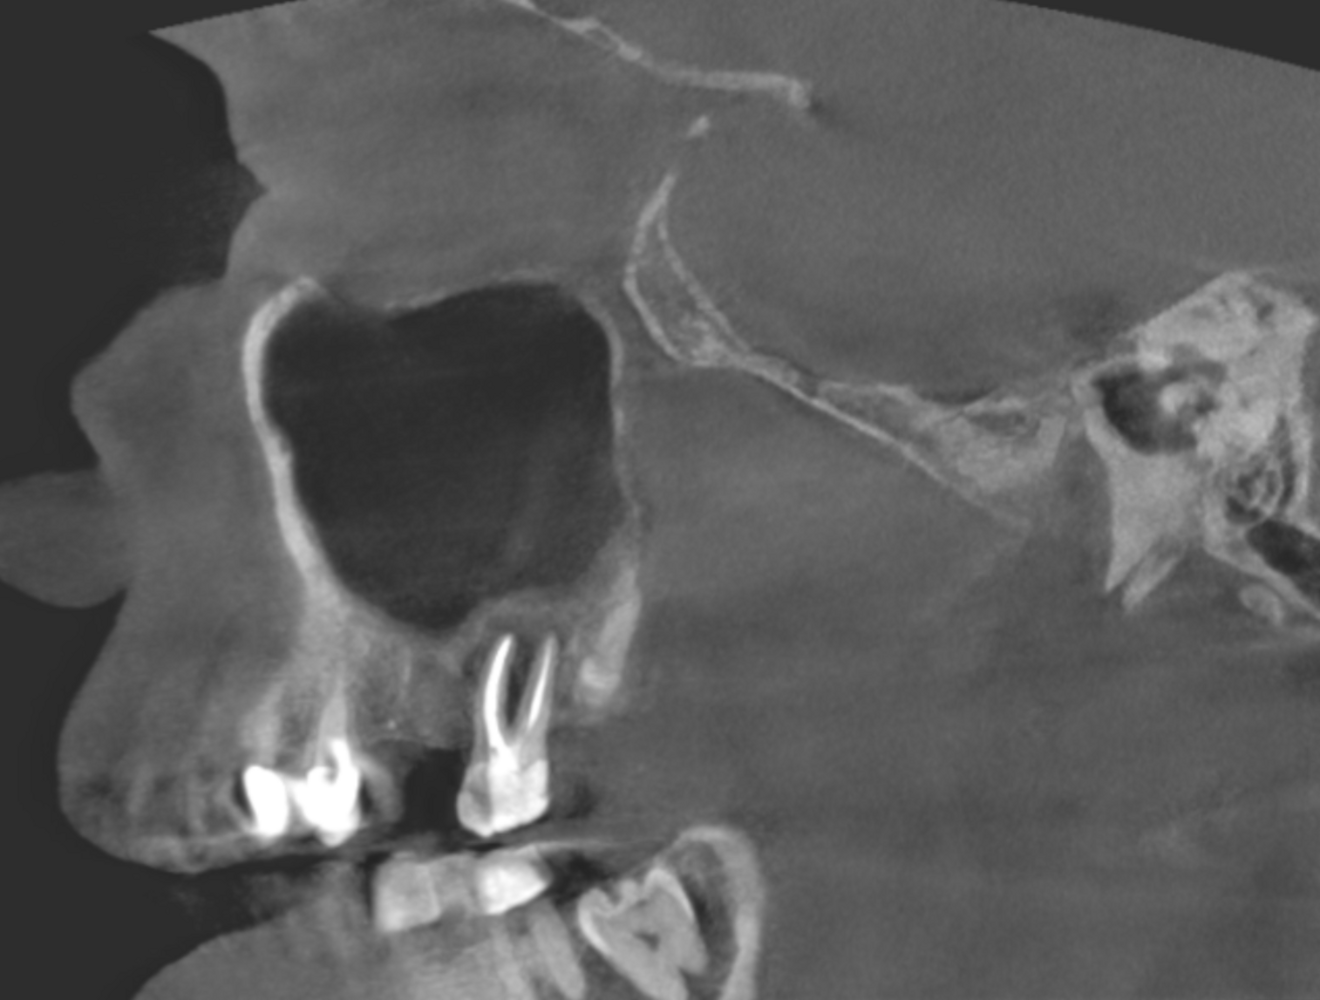

Fig. 2a: Large-volume CBCT scan, sagittal cross-section of the buccal roots.

Fig. 2b: Large-volume CBCT scan, sagittal cross-section of the palatal root.